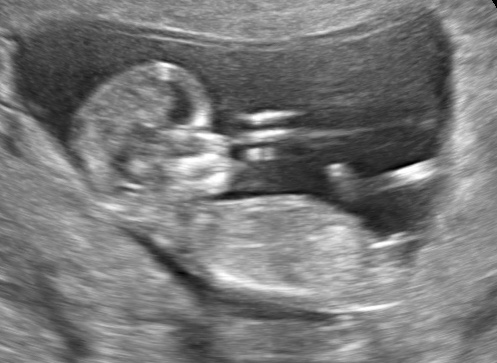

37 weken

Een echo na 37 weken.